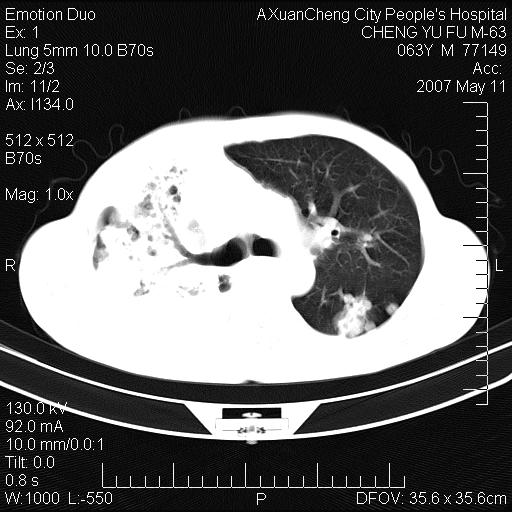

以下是引用小初学者在2007-5-11 19:32:00的发言:[br]1、首先考虑干酪性肺炎支气管播散[br]2、支气管肺泡癌待排

以下是引用zhangzhongshou在2007-5-11 19:30:00的发言:[br]细支气管肺泡癌可能性大。